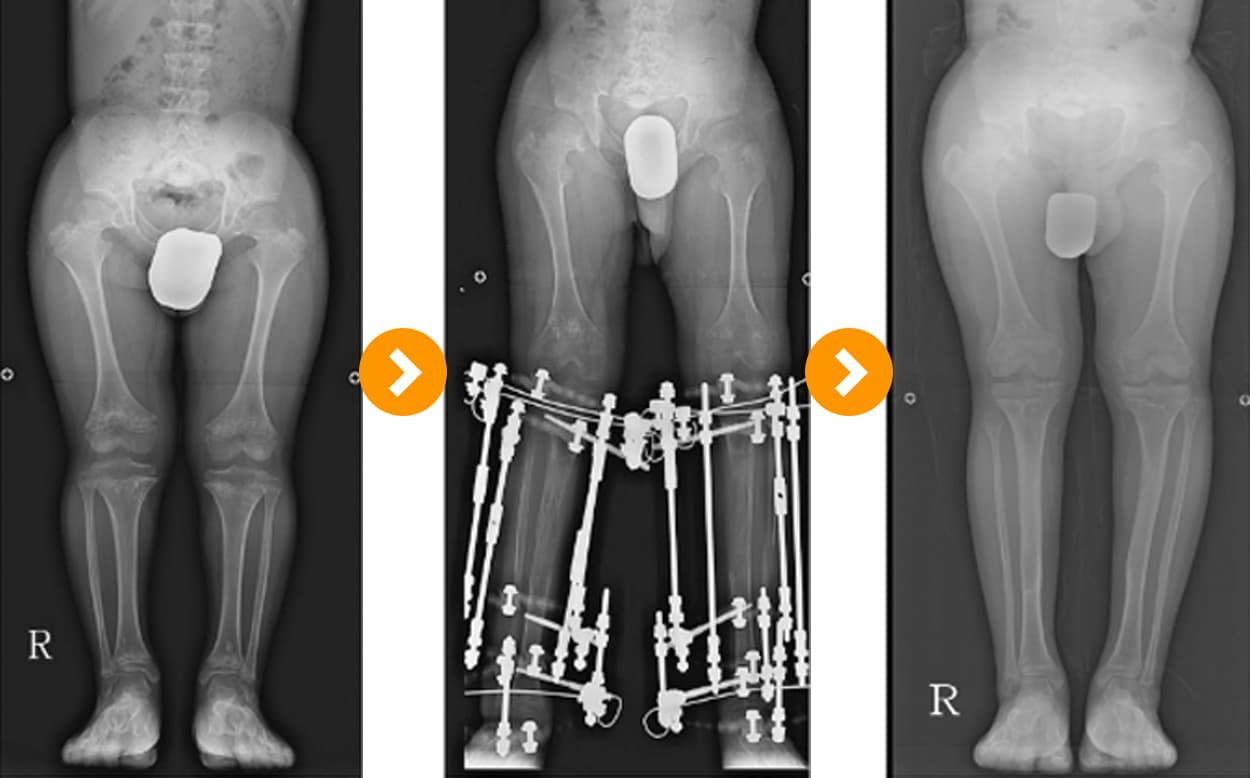

연골 무형성증오다리교정 및 골연장술 10cm